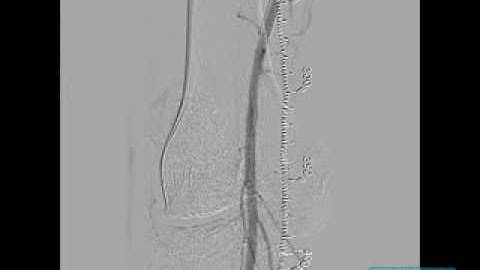

Mid SFA CTO Treated with Cross Boss #1